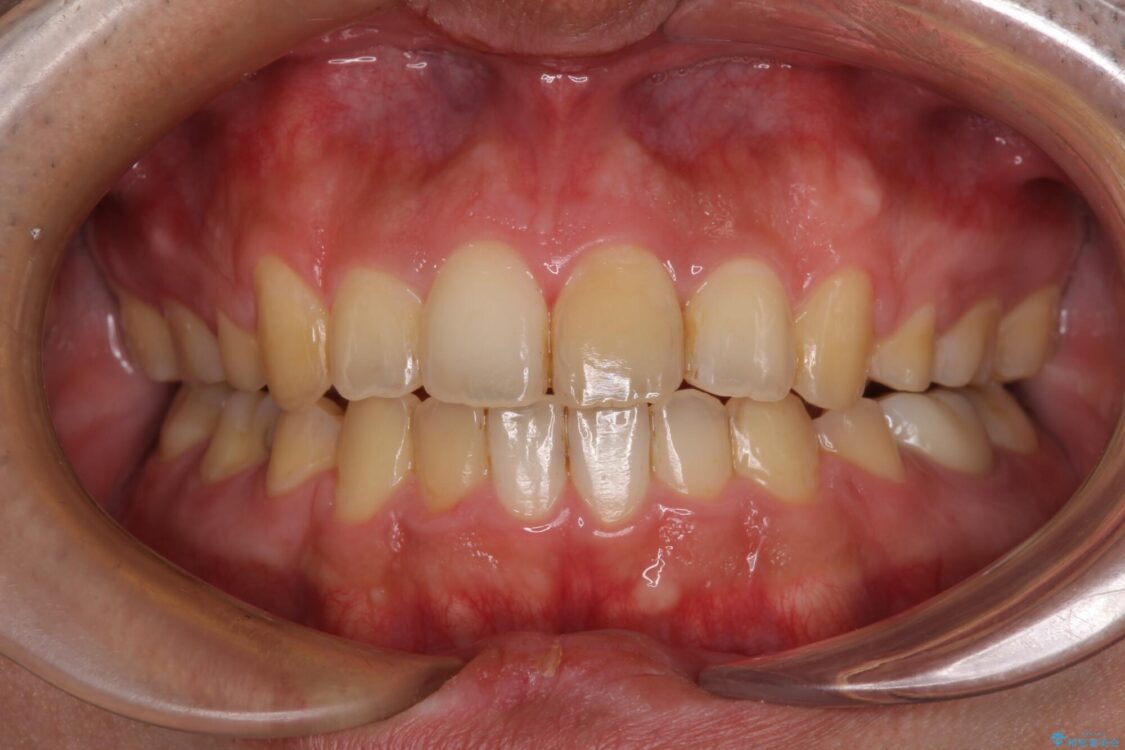

高校時代に行った抜歯矯正が後戻りをしたとのことで来院された患者様です。

再矯正であることから、目立ちにくい装置を希望されたため、インビザラインにて矯正治療を行うこととしました。

治療前

• 後戻りでデコボコの前歯 インビザライン矯正治療 治療前画像